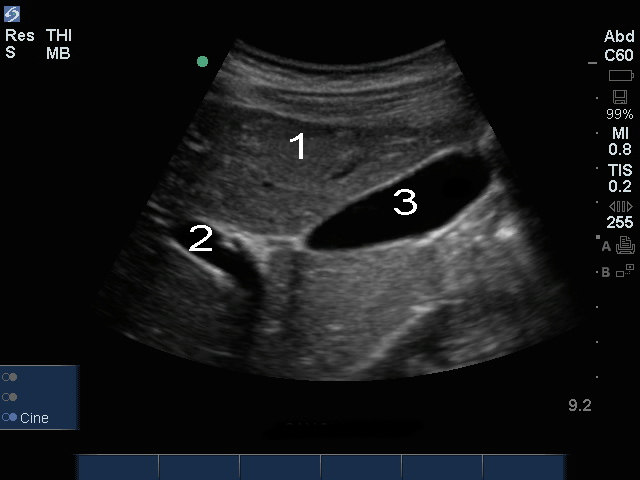

胆囊门静脉图像

肝脏

门静脉 (PV)

胆囊 (GB)